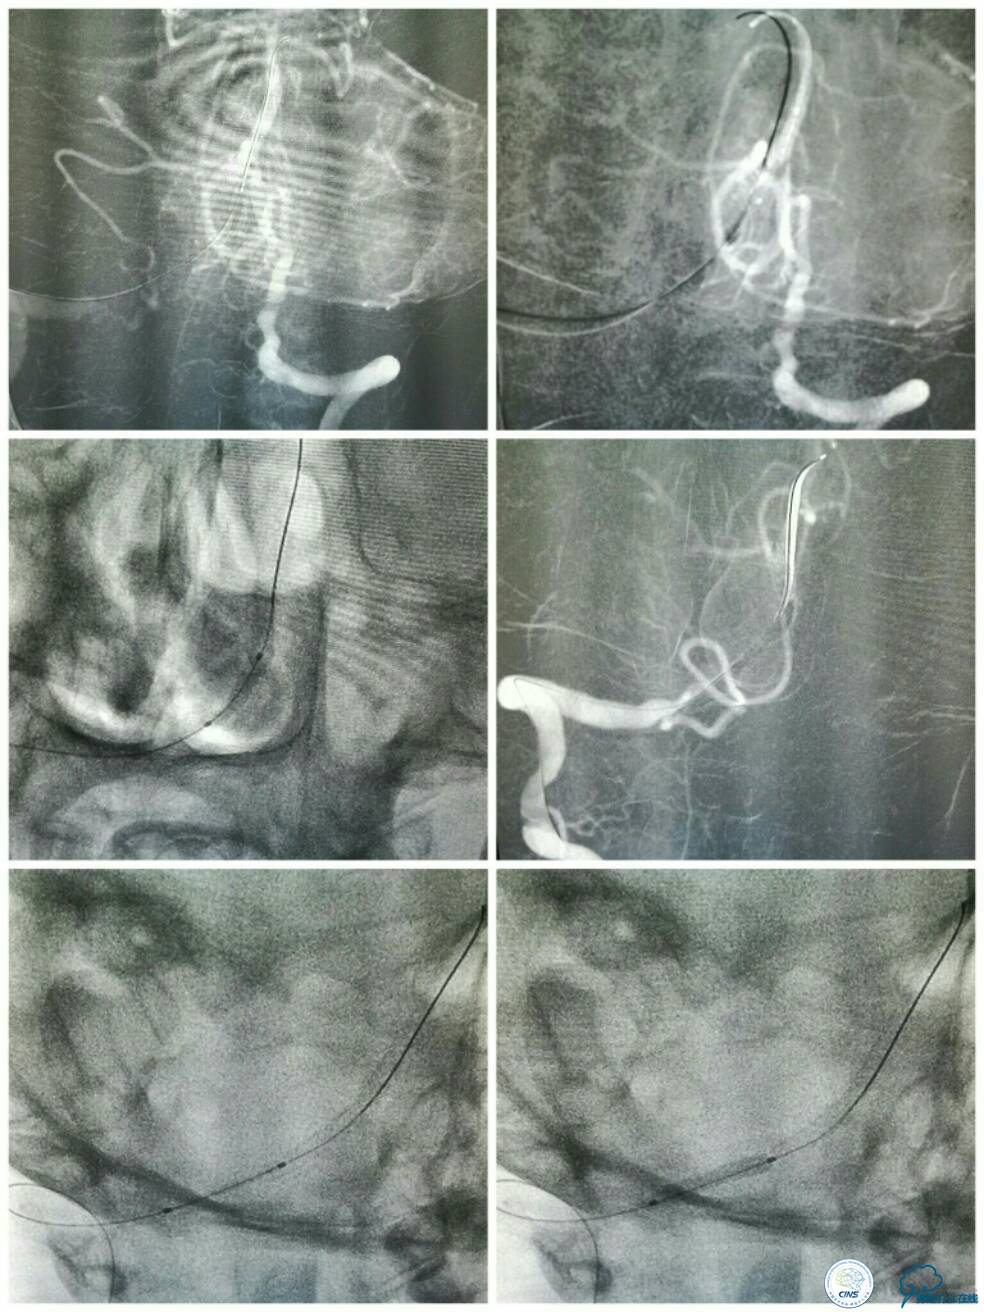

微导管造影证实在基底动脉真腔后,交换技术送入Transend微导丝(0.014″300 cm)至左侧大脑后动脉P1段,送入Gateway球囊(2.0 mm×9.0 mm)从闭塞段远端向近心端扩张4次,扩张完造影示右椎动脉V4段无再通(图9)。

此时经6F导引导管和放置在左椎动脉V1段的5F椎动脉造影导管行双路径图,以显示椎基底动脉系统。选用Apollo球囊扩张支架(2.5 mm×13 mm 3枚,3.0×8 mm 1枚)自闭塞远端至近端依次释放支架,两个支架间重叠约2 mm(图10)。